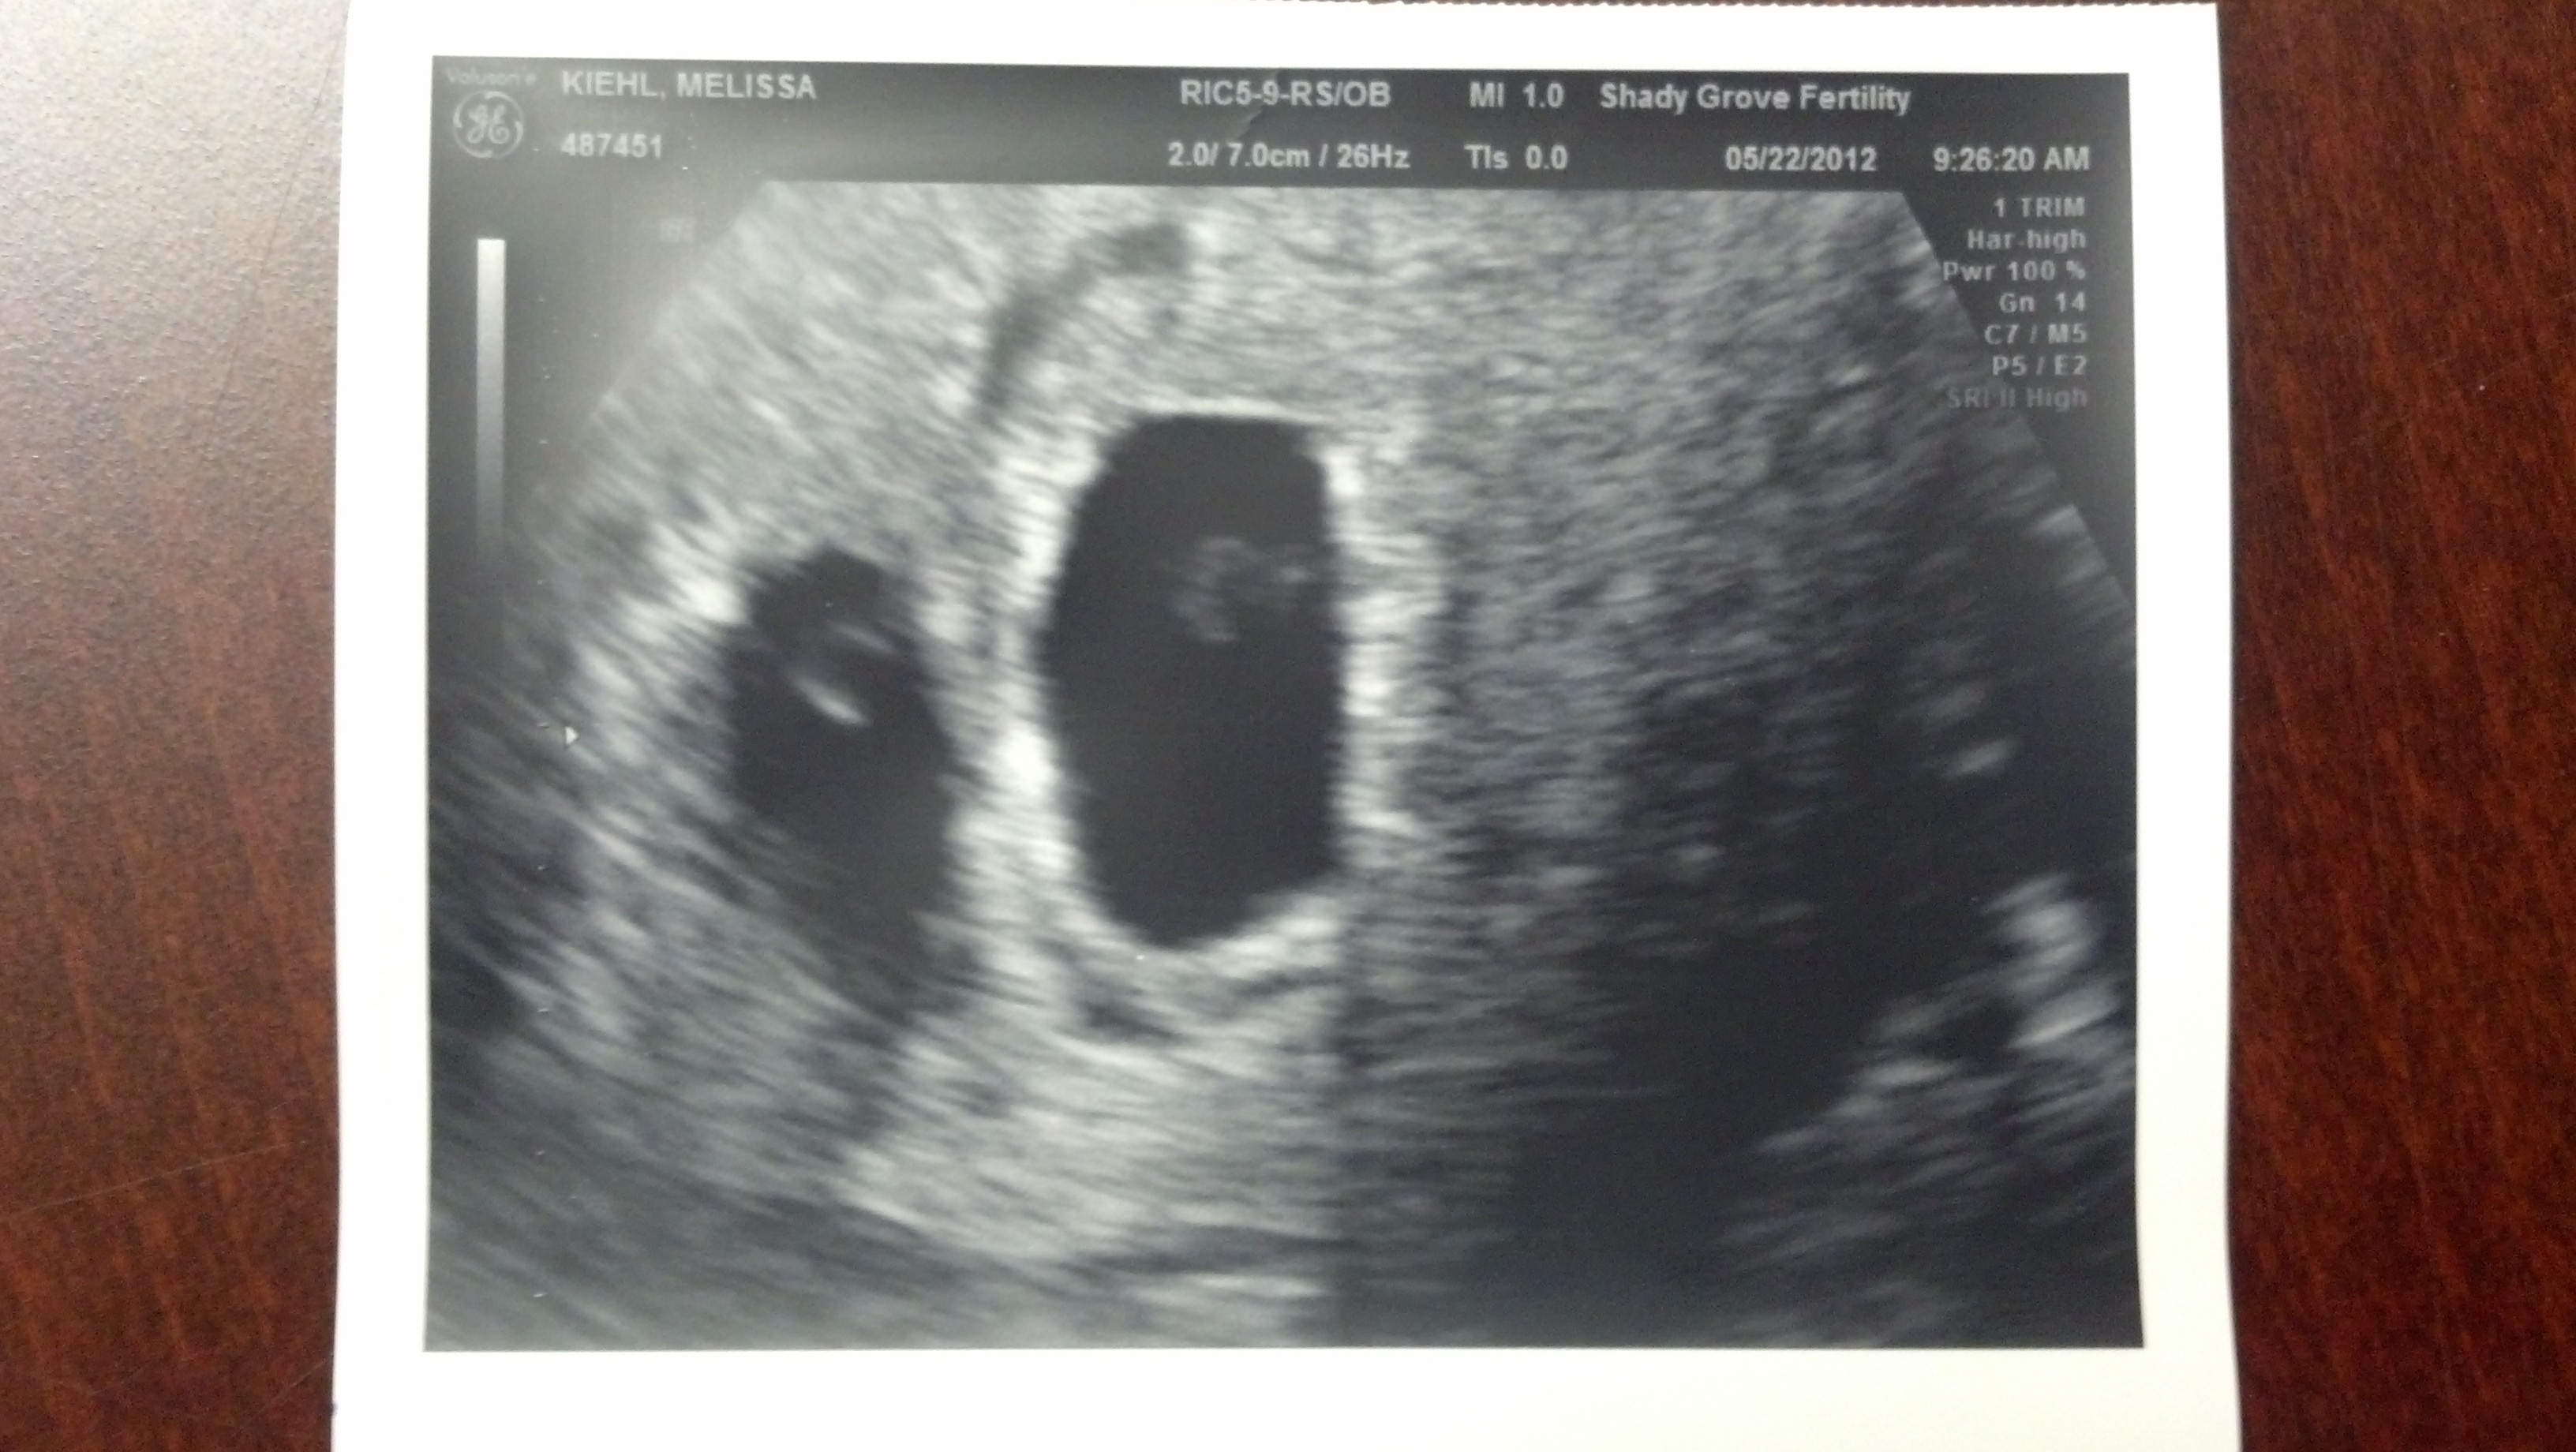

May 22, 2012 - The 1st ultrasound - Guess who's having twins!